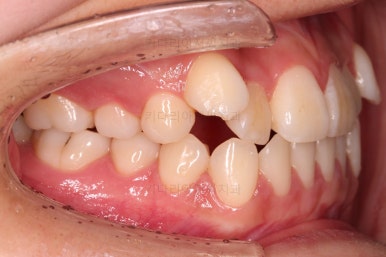

입 안을 보면 밑에 치열이나 다른 부분은 비교적 양호한데 유달리 윗니 송곳니만 위치가 좋지 못하네요.

비발치

이번 환자분은 보기에는 송곳니가 덧니라 많이 삐뚤어 있는 것 같지만 치료는 비발치, 즉 발치 없이 진행했는데요.